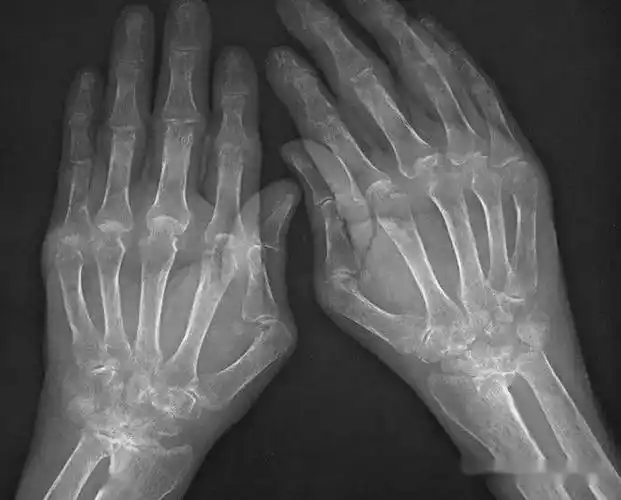

手指关节疼痛,肿胀,关节内有骨性增长物(骨刺).

手指骨关节炎